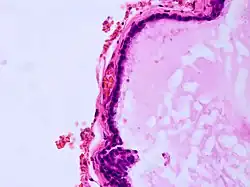

Histopathology of colloid cyst

A colloid cyst is a non-malignant tumor in the brain. It consists of a gelatinous material contained within a membrane of epithelial tissue. It is almost always found just posterior to the foramen of Monro in the anterior aspect of the third ventricle, originating from the roof of the ventricle. Because of its location, it can cause obstructive hydrocephalus and increased intracranial pressure. Colloid cysts represent 0.5–1.0% of intracranial tumors.[1]